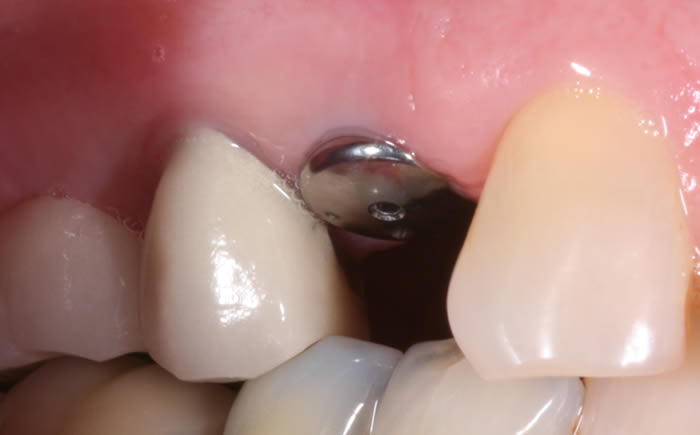

More back teeth replaced by dental implants

Case Three (2 images)

Case Four (4 images)

Case Five (4 images)

Case Six (8 images)

Case Seven (4 images)